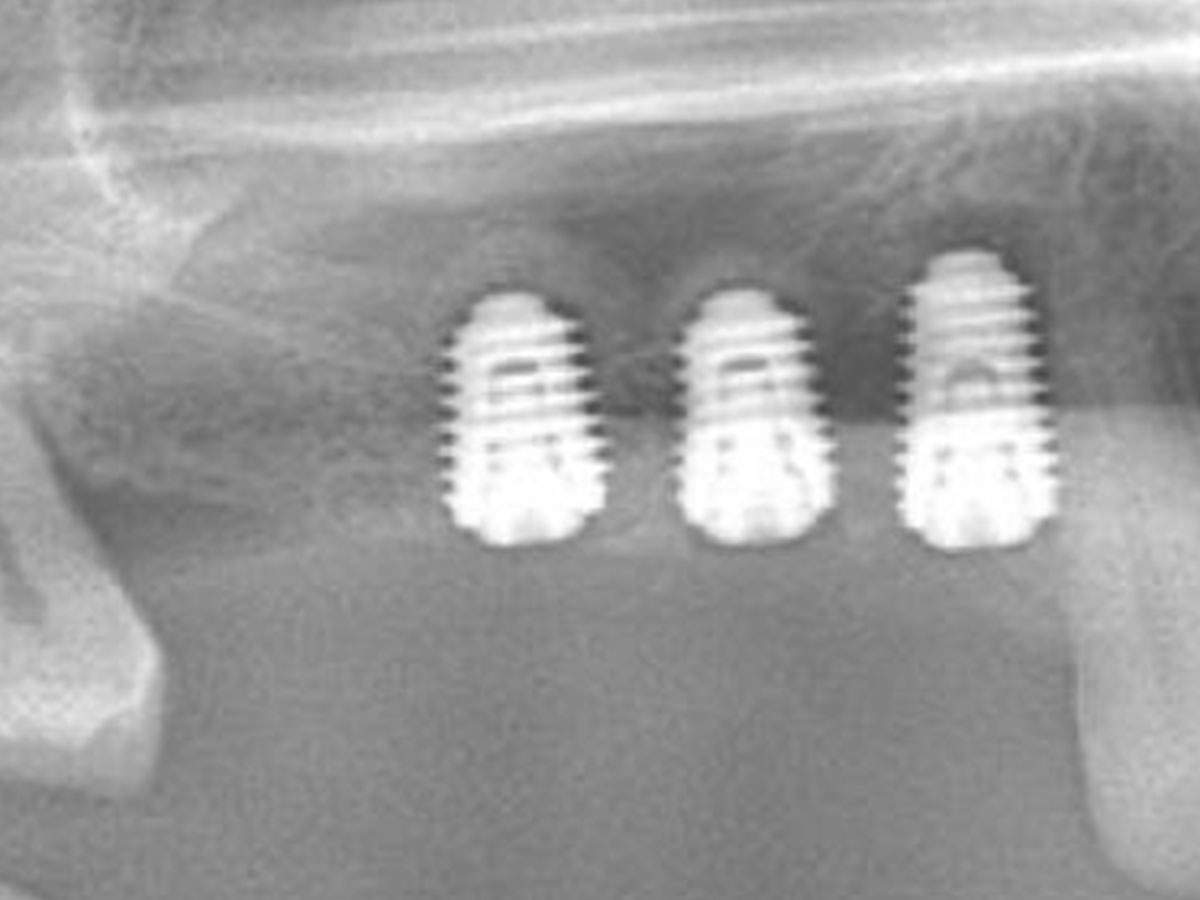

· Biologische Grundlagen der Knochenverdichtung mit Densah-Bohrern (Osseodensification): Prinzip, Anwendung und Vorteile

· Indikationen bei geringem Knochenangebot und Sinusnähe